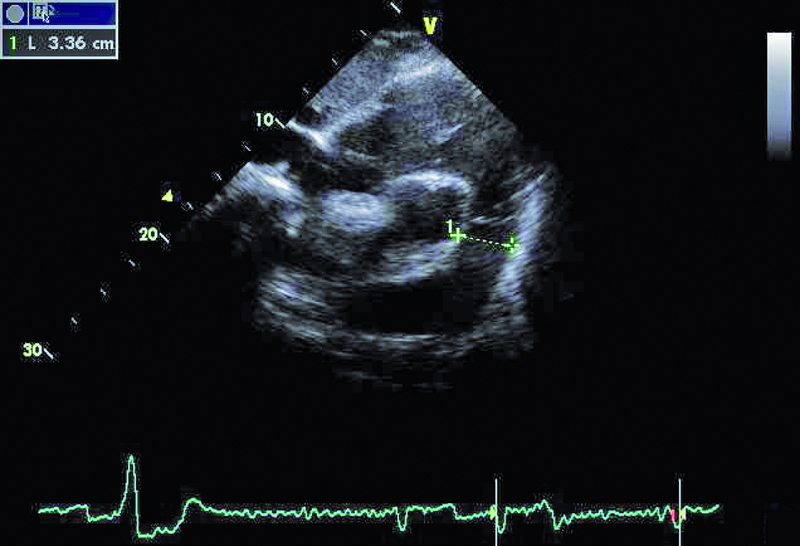

Kobieta, lat 80. Jakie patologie można rozpoznać na rycinach?

3. Poszerzenie pnia płucnego (ryc. 2).